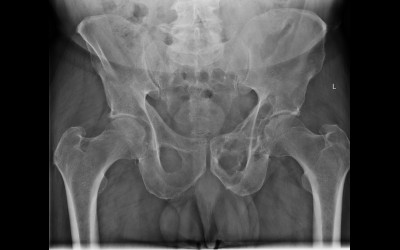

Röntgenfall des Monats April 2017 mit Auflösung

76 jähriger Patient mit diffusen Skelettschmerzen Keine Grunderkankung bekannt, kein Trauma.

Becken ap